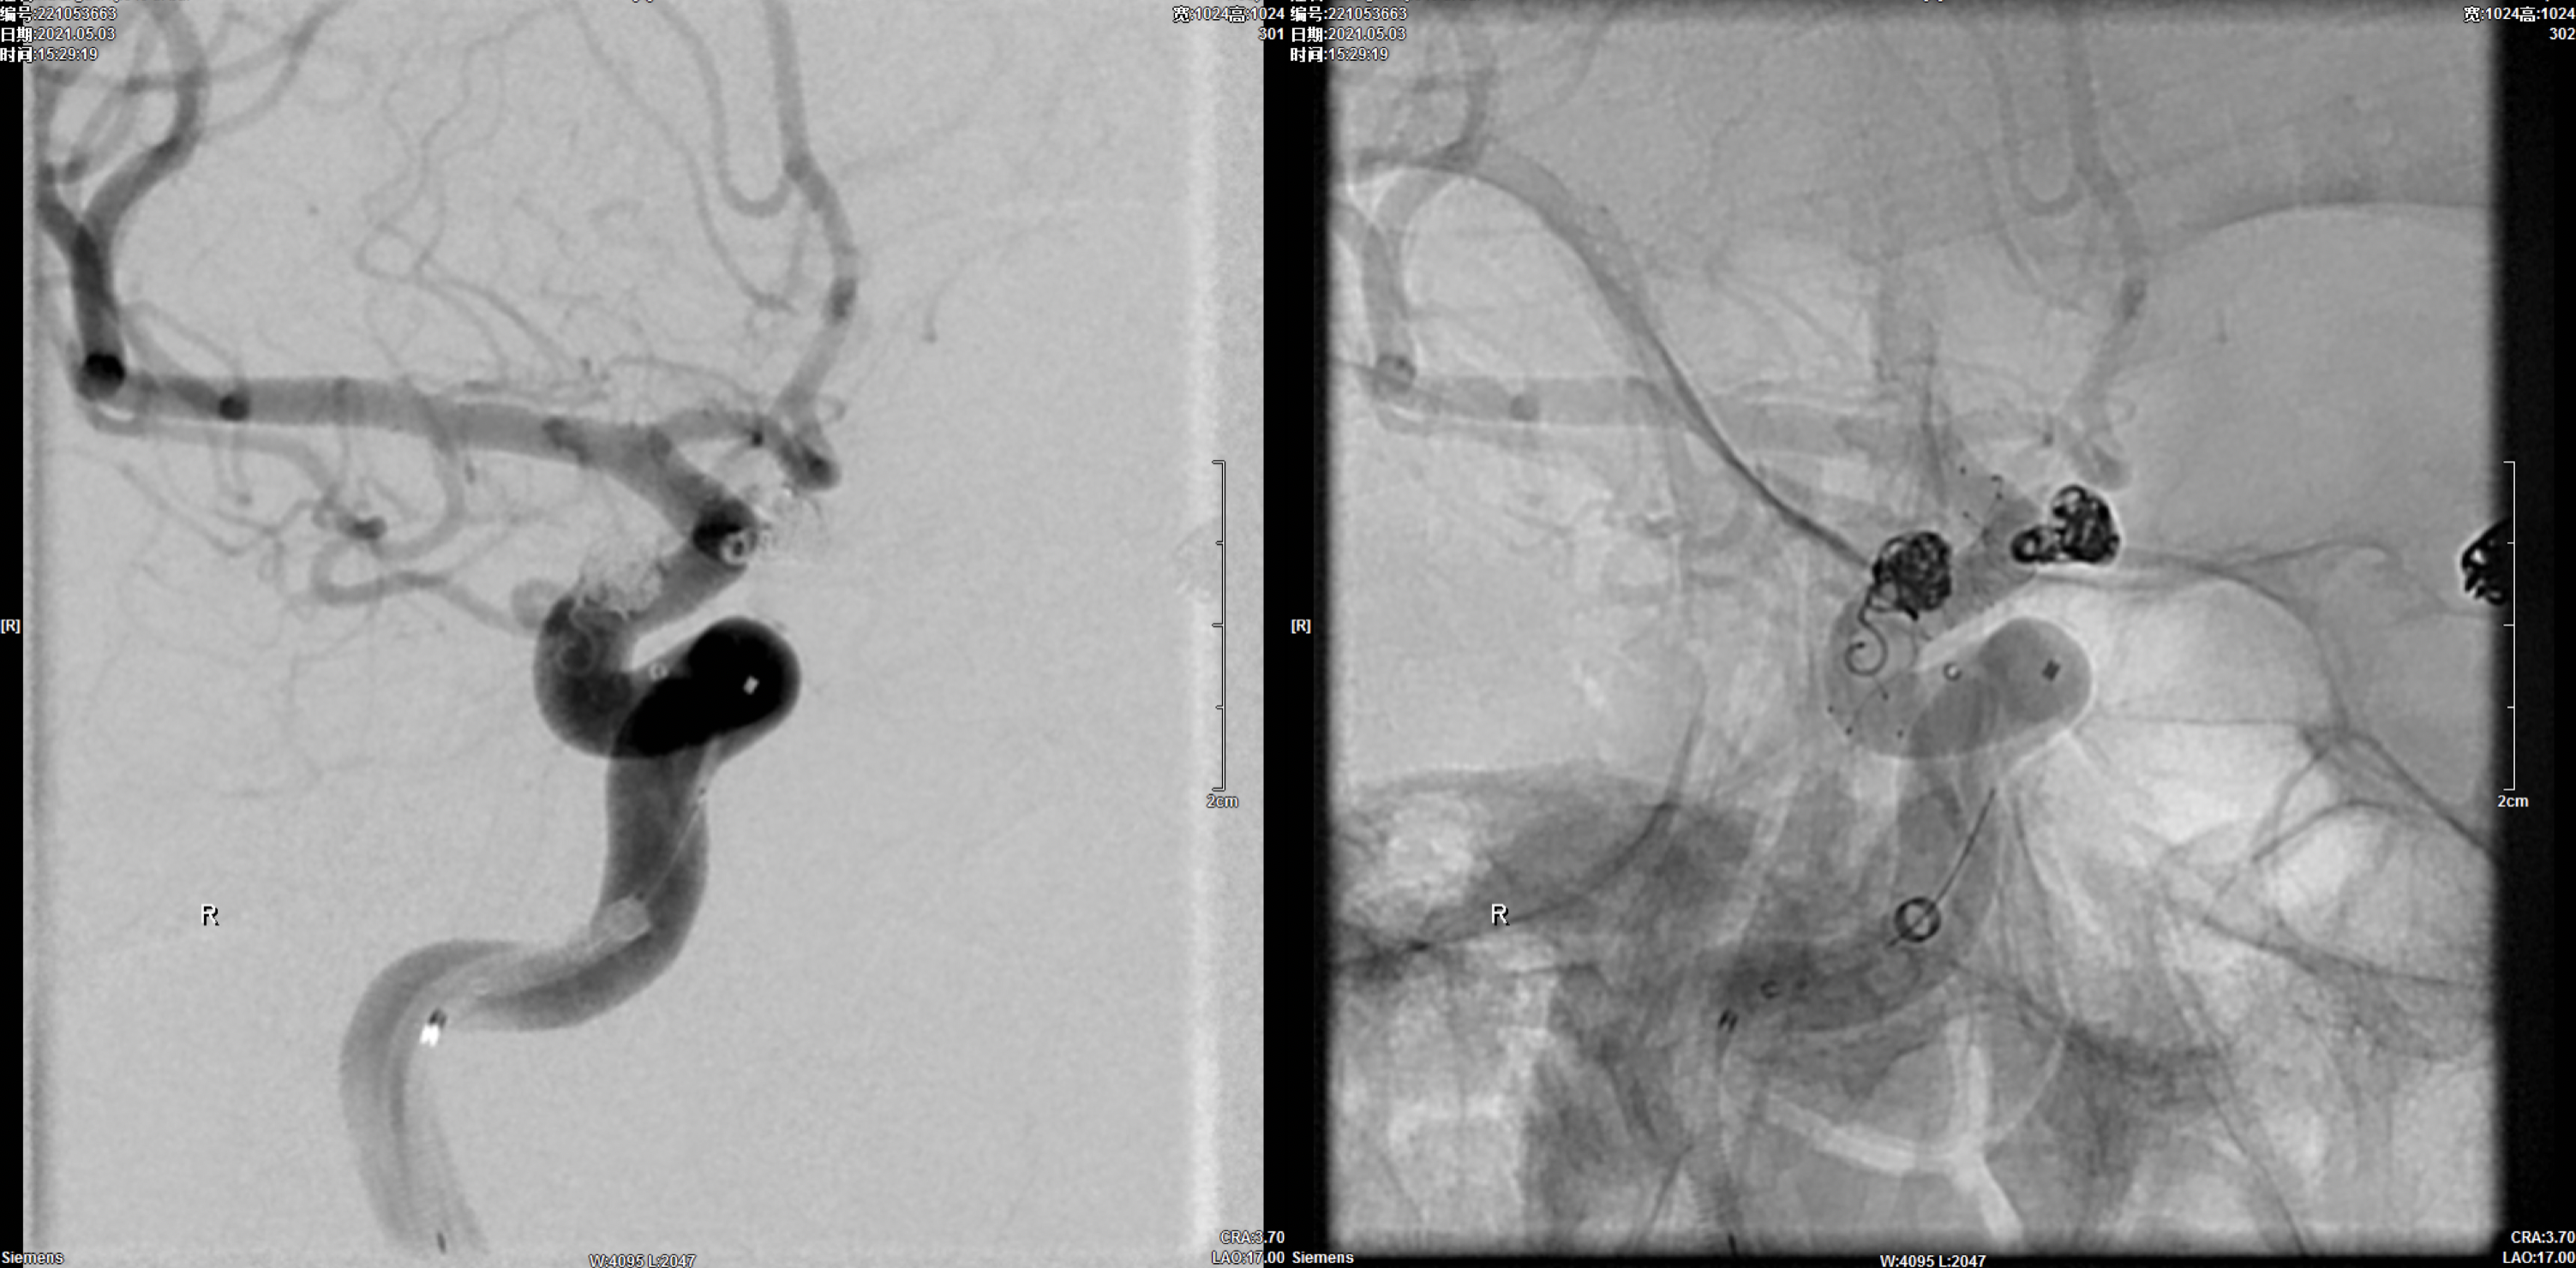

右侧颈内动脉三维重建:颈内动脉多发动脉瘤(眼动脉段及后交通段)

7F长鞘+6F Navien建立左侧颈内动脉栓塞通路后,栓塞微导管超选进入动脉瘤瘤腔内。

行单纯栓塞,工作位造影及蒙片显示:动脉瘤栓塞完全!撤除栓塞导管。